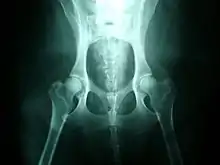

Hip dysplasia is diagnosed with radiographs of the pelvis. There are several standardized systems for categorising dysplasia, set out by reputable bodies. The most widely used systems include the following:

Radiographs can be sent to OFA for grading and certification.[11] This system rates a dog's hip joint on a seven-point scoring system. The test relies on interpretation of a radiograph of the dog's hips, which are then assigned a score by three independent radiologists: Excellent, Good, Fair, Borderline, Mild, Moderate and Severe.[12]